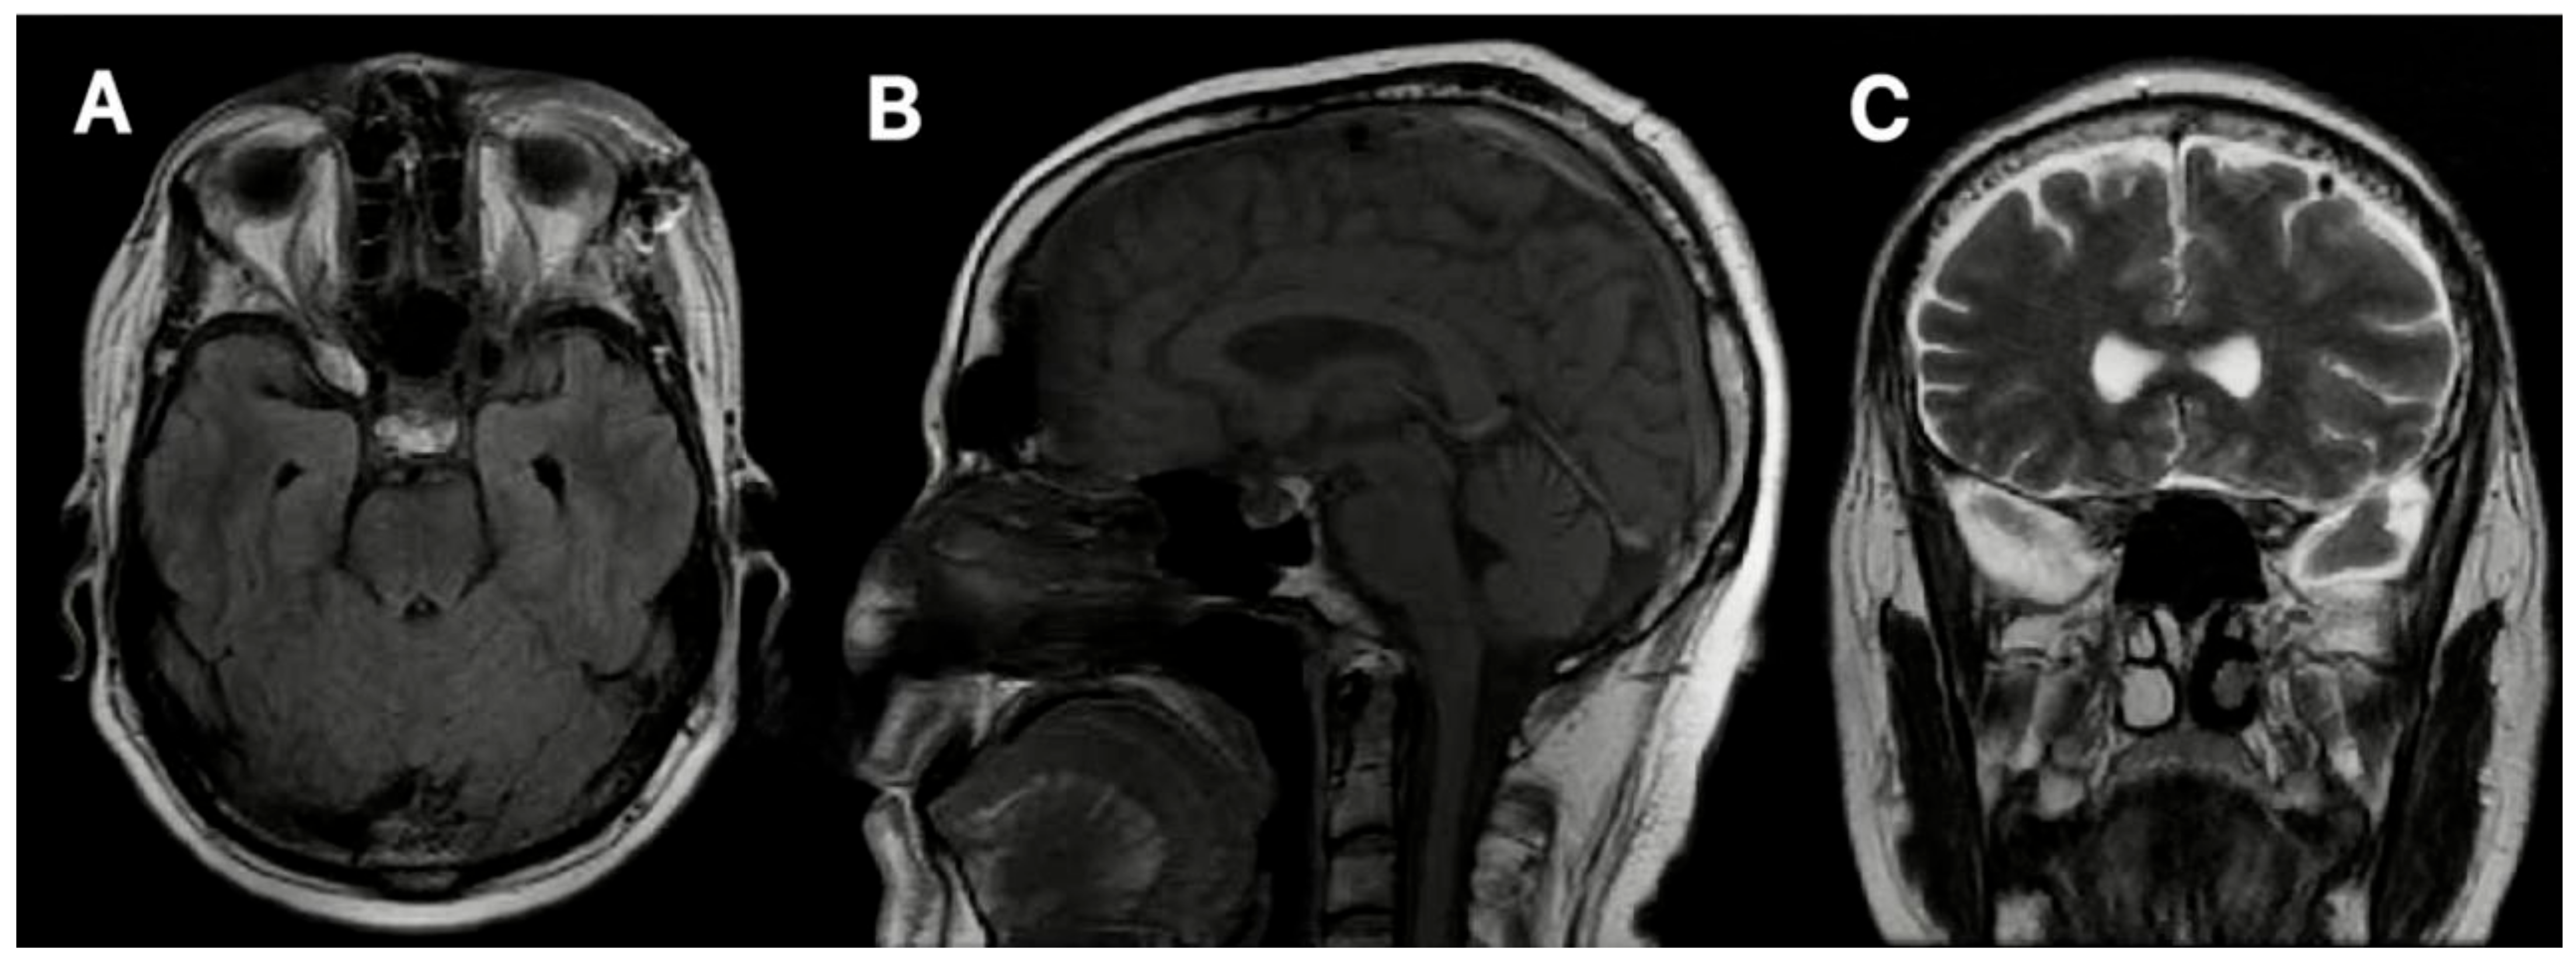

3.2. Case 2

3.2.1. Demography, Presentation, and Evaluation

3.2.2. Intervention

3.2.3. Postoperative Period